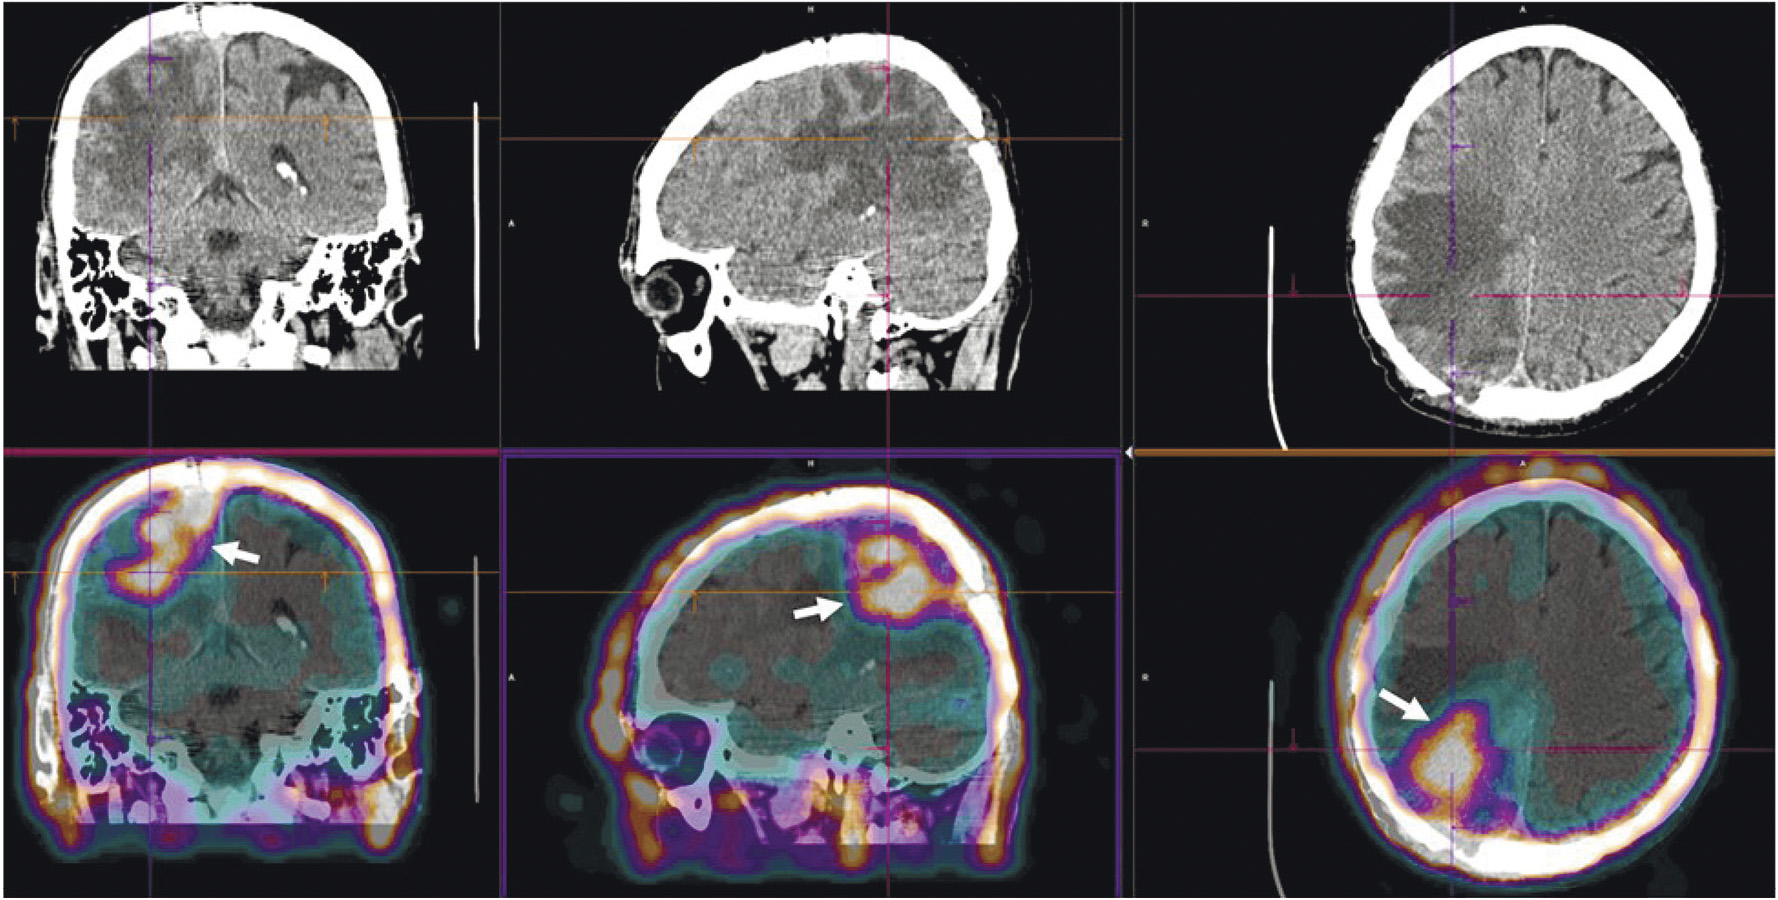

Радиофармпрепарат 99mTc-1-Тио-D-глюкоза и набор для его приготовления разработаны в НИИ онкологии Томского НИМЦ и ТПУ (“Тиоскан, 99mТс”, Россия). Неповреждённый гематоэнцефалический барьер непроницаем для данного препарата, поэтому 99mTc-1-Тио-D-глюкоза хорошо показала себя в диагностике опухолей головного мозга (рис. 7) [43]. Кроме того, ОФЭКТ/КТ с 99mTc-1-Тио-D-глюкозой рекомендована для стадирования и прогноза результатов лечения лимфопролиферативных заболеваний (рис. 8) [44, 45].

Рис. 7. ОФЭКТ/КТ с 99mTc-1-Тио-D-глюкозой пациента с рецидивом глиобластомы. Стрелками обозначено накопление РФЛП в опухоли